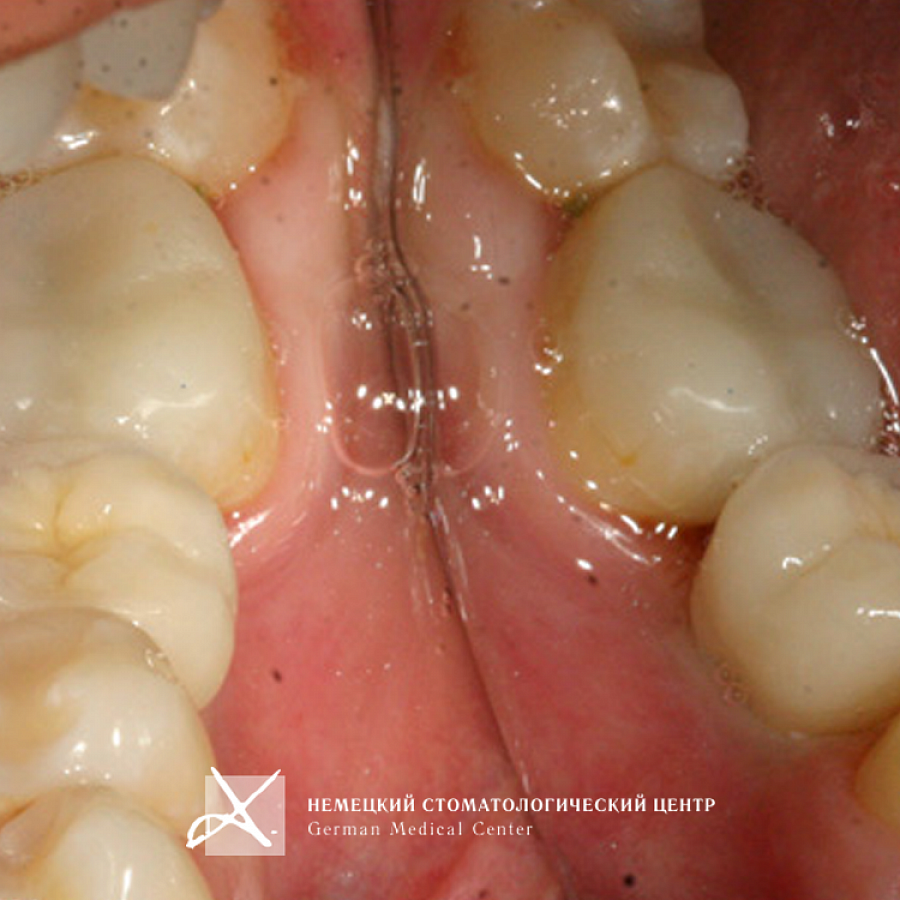

Пациентка обратилась с жалобой на отсутствие зуба 36.

1. Проведена имплантация отсутствующего зуба.

2. Для оптимальной эстетики была изготовлена коронка с каркасом из оксида циркония с использованием индивидуального абатмента, выполненного из аналогичного материала по технологии CAD/CAM. Диоксид циркония (ZrO2) обладает высочайшей степенью биологической совместимости.